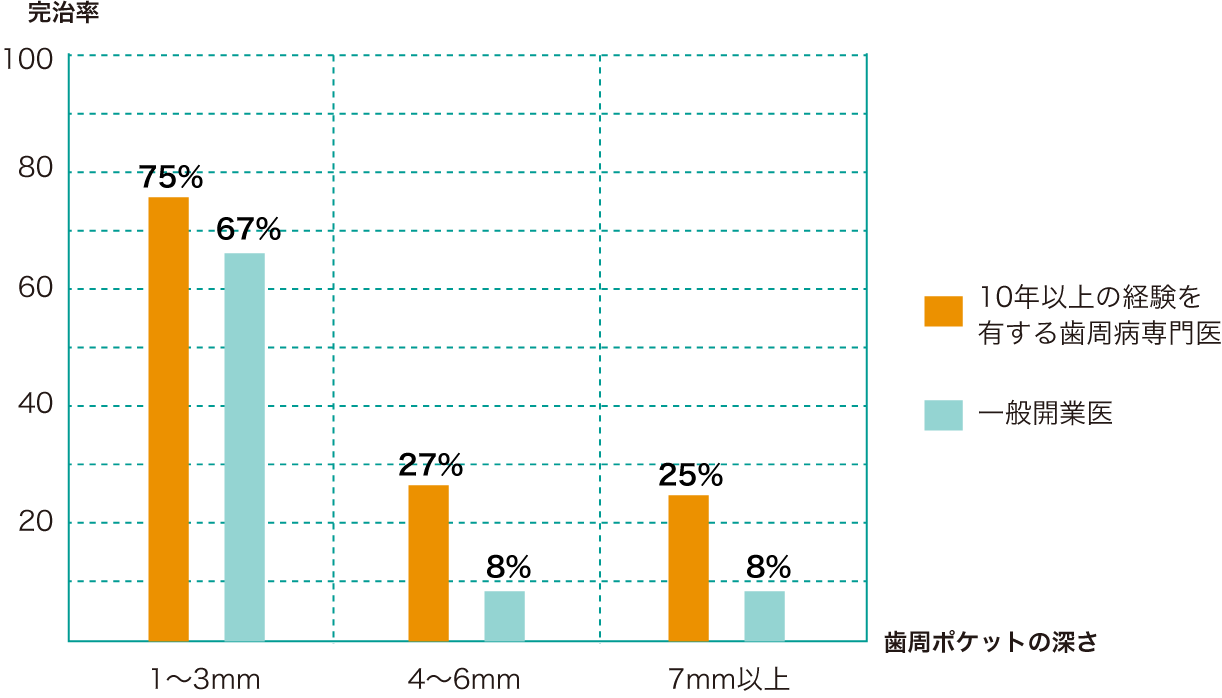

進行した歯周病の治療法

進行した歯周病は初期治療では治らない場合もあります。歯周ポケットが深いところは器具が届かないところがあるからです。溝が深くなればなるほど器具の到達率な低下し歯石は取り残しになります。

歯周病外科処置

歯周初期治療後改善しない場合、歯茎を切開して深いポケットの歯石を取ります。

■骨を滑らかにする。プラークコントロールをしやすい環境を作る。

■道路の側溝は汚れがいっぱい、歯周病でできた骨のがたがたを放置しておくとばい菌で一杯になり、歯周病が再発します。

■歯周病は歯茎に隠れた骨の病気なのです。

■歯周外科手術でなるべく骨をなだらかしてお掃除のしやすい形態に変えていきます。